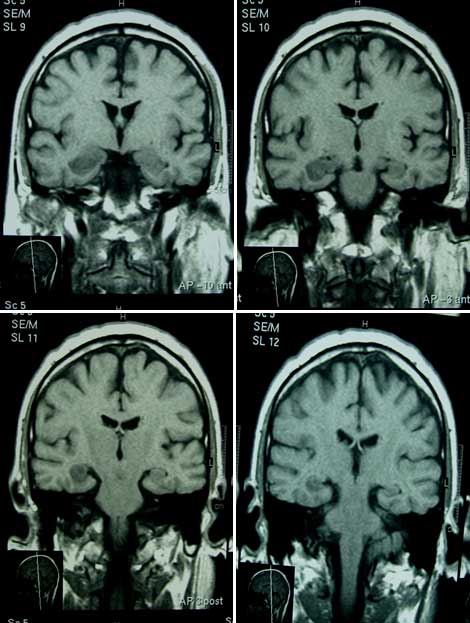

IRM T1 coronal: Encefalitis límbica: hipointensidad amígdalo-hipocampal bilateral de predominio derecho.